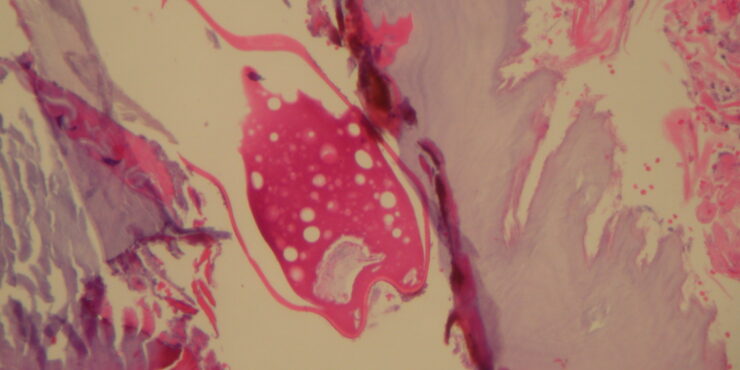

Tungiasis =داء الطوامر Tungiasis Tungiasis is an infestation by the burrowing flea Tunga penetrans or related species. The flea has many common names as listed above. Tungiasis was first reported in crewmen who sailed with Christopher Columbus. The flea is indigenous to the West Indies/Caribbean/Central America region, but it has spread to Africa, India, Pakistan, and South America. Travelers to endemic areas […]